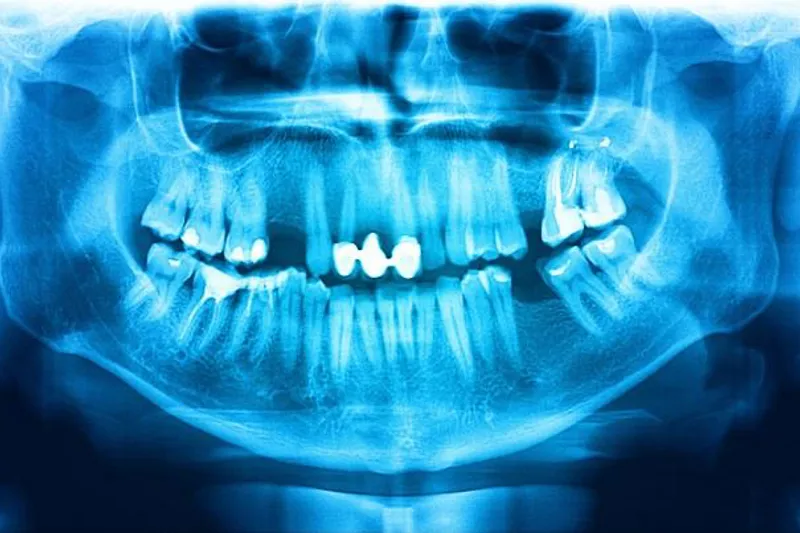

Panoramaoptagelser

Foto: Shutterstock

Græske forskere har udgivet en systematisk oversigt om indikationer for anvendelse af panoramaoptagelser inden for børnetandpleje. Kun 16 tidligere publicerede undersøgelser levede op til inklusionskriterierne, og de var fordelt på seks forskellige indikationsområder (caries, akutte infektioner, tandtraumer, dentale anomalier, udviklingsforstyrrelser og patologiske tilstande), så hovedkonklusionen blev, at der mangler primær forskning af tilstrækkelig kvalitet på området.

I forbindelse med cariesdiagnostik noterede man, at der registreres flere carieslæsioner ved klinisk undersøgelse end ved hjælp af panoramaoptagelse. I en kommentar til oversigten hæfter britiske forskere sig ved, at undersøgelsens resultater er i overensstemmelse med de britiske retningslinjer, som anbefaler en kombination af klinisk undersøgelse og bitewingoptagelser i forbindelse med cariesdiagnostik.

De påpeger endvidere, at panoramaoptagelser kun bør komme i betragtning ved diagnostik af traumer, infektioner og andre patologiske tilstande, hvis intraoral optagelser med lavere stråledosis ikke giver tilstrækkelig information til at danne grundlag for kliniske beslutninger.